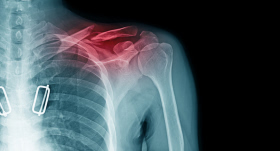

• Lūzums